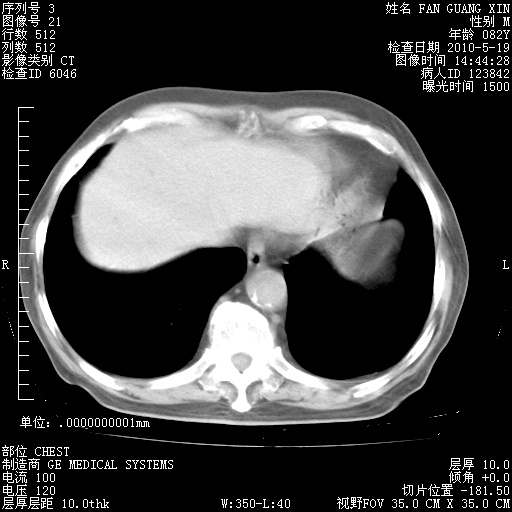

再治疗10天后的肺部CT

再治疗10天后的肺部CT 纵膈窗

阅读此次胸部CT,肺间质渗出性改变较入院时有吸收。目前从体温、白细胞、中性分叶明显增高,肯定存在细菌感染(发生医院感染哦,若无消化道及泌尿系统等感染的依据,肺部感染可能大)。若你院头孢哌酮舒巴坦钠耐药率较高,同意你的方案,若48小时体温仍高,可考虑使用碳青霉稀类抗菌药物,同时可予超声雾化、注意滴数时加大液体量。白蛋白33.30g/L较低哦,需加强营养等支持治疗。